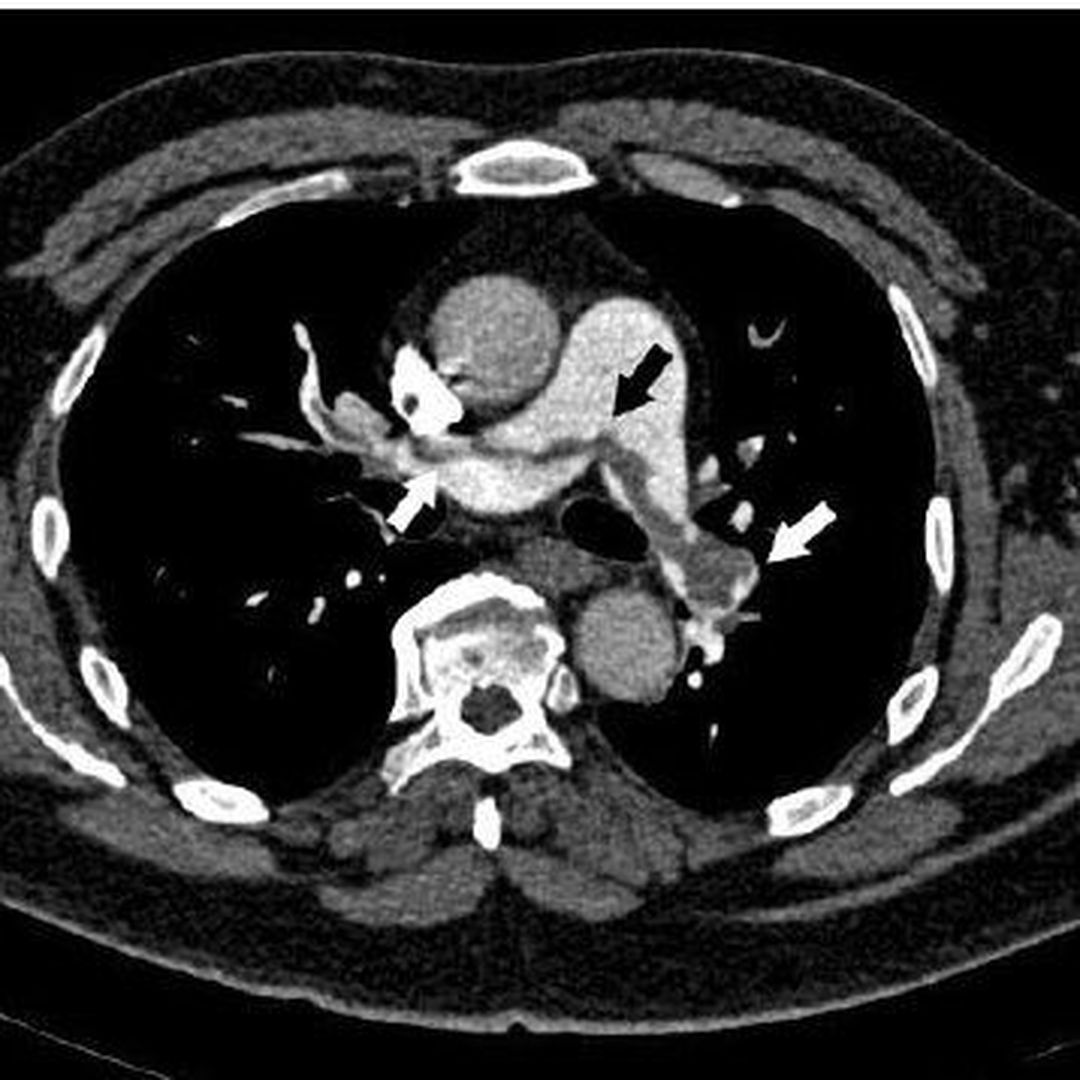

Pulmonary embolism is a potentially life-threatening condition, which occurs due to dislodging of deep vein thrombus/thrombi, resulting in blockage of pulmonary artery. Most common cause of pulmonary embolism is deep vein thrombosis. Pulmonary artery may also be blocked by fat embolism, air embolism, or a fragment of tumor. The symptoms usually depend on the size of the thrombus and the area of the lung involved as well as the comorbidities of the patient. Most common signs and symptoms are: - Shortness of breath: Sudden; worsens with exertion - Chest pain: Sharp pain associated with breathing; cough and bending over also worsen the pain - Cough: Associated with blood-streaked sputum - Irregular, rapid heartbeat - Loud S2 is heard on auscultation. S3 gallop may also be present. - Dizziness - Fever - Sweating - Cold, clammy and/or cyanotic skin Risk factors of pulmonary embolism are: - Family history of pulmonary embolism - Cardiovascular disorders e.g., heart failure - Malignancy: brain and ovarian tumors, CA pancreas, stomach cancer colon cancer, and malignancy of kidneys are associated with increased risk of blood clot formation - Surgery and bed rest: Prolonged immobilization increases risk of deep vein thrombosis and subsequent risk of embolism - Hypercoagulable states - Coivd-19: people with severe symptoms might develop pulmonary embolism - Smoking - Obesity - Pregnancy and estrogen supplements Diagnosis is based on detailed history, with emphasis on comorbidities, travel, and surgical history. Laboratory panel includes blood tests to look for elevated levels of D-dimers indicative of blood clots, hereditary conditions causing blood clots formation, and blood gases. The gold standard diagnostic modality for pulmonary embolism is pulmonary angiogram. Ultrasound, to look for deep vein thrombosis, and CT Chest with contrast is done to look for pulmonary embolism. Ventilation/perfusion scan may be done in case where contrast is contraindicated. MRI may be used for diagnosis in pregnant women where radiations should be avoided. The medical management of pulmonary embolism involves administration of anticoagulants and thrombolytics. Heparin is the most common used anticoagulant. Warfarin is also given orally as adjunct. Surgical options include insertion of vein filter to prevent passage of clot from legs to right side of heart or removal of clot if it is life-threatening and large in size via flexible catheter. Source Pulmonary embolism https://www.mayoclinic.org/diseases-conditions/pulmonary-embolism/diagnosis-treatment/drc-20354653 Image via https://en.wikipedia.org/wiki/Pulmonary_embolism